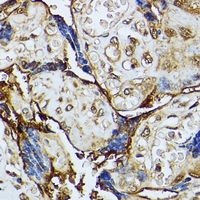

Immunohistochemical analysis of DAP Kinase 3 staining in human placenta formalin fixed paraffin embedded tissue section. The section was pre-treated using heat mediated antigen retrieval with sodium citrate buffer (pH 6.0). The section was then incubated with the antibody at room temperature and detected using an HRP conjugated compact polymer system. DAB was used as the chromogen. The section was then counterstained with haematoxylin and mounted with DPX. -